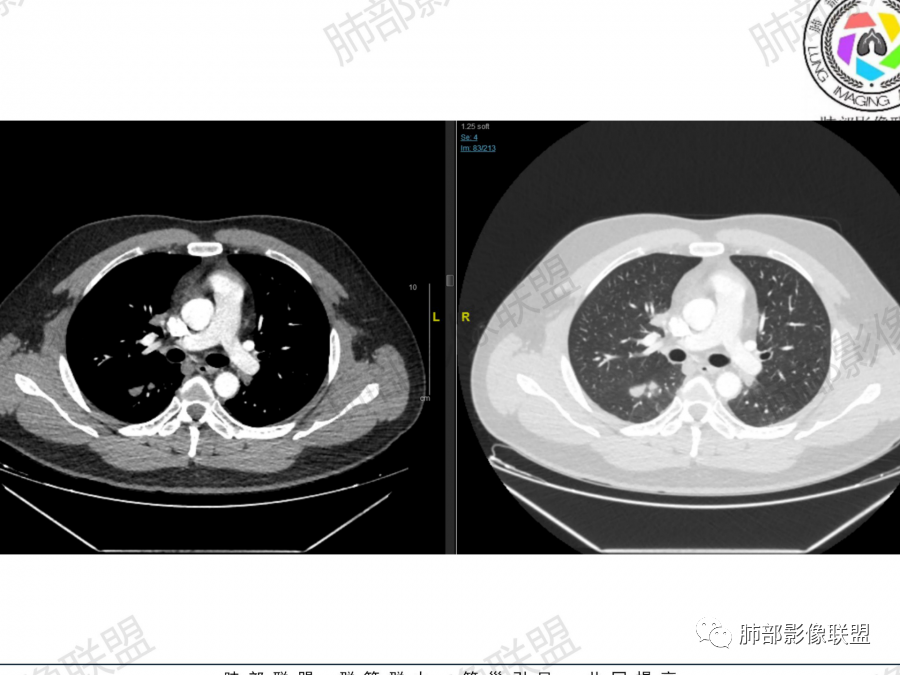

1.右上肺团块:分叶,不均性强化,其内支气管走行自然,增强血管影可见、清晰。

疑问:空洞还是残余肺组织?

右上肺实变,血管造影征、支气管充气征

这个增强后有不均匀坏死

2、右肺多发结节影,大者位于右肺上叶尖段,内可见空洞,空洞内壁欠规整,内可见分隔,余结节位于胸膜下、结节大小不等、形态相近,强化均匀,内部可见血管穿行,血管及支气管走行自然。结合临床及影像,符合隐球病。